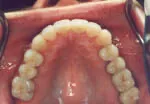

Inlays and onlays are tooth-colored restorations that are used in place of silver fillings on the chewing surfaces of back teeth. Unlike silver fillings made from metals that may cause further damage to teeth, these cosmetic fillings look extremely natural and typically require that far less of the tooth be removed.